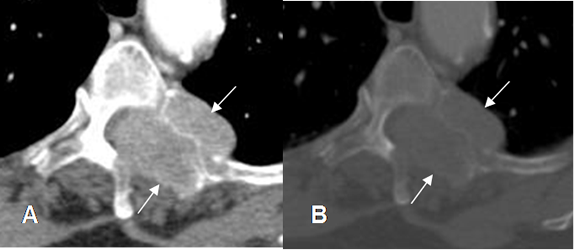

Fig 153. Metástasis líticas.

A: TAC axial en ventana de tejido y B: TAC axial en ventana osea. Lesión lítica que compromete los elementos posteriores en el lado izquierdo, por metástasis de neoplasia renal. Hay masa de tejidos blandos, que se extiende hacia el canal medular.